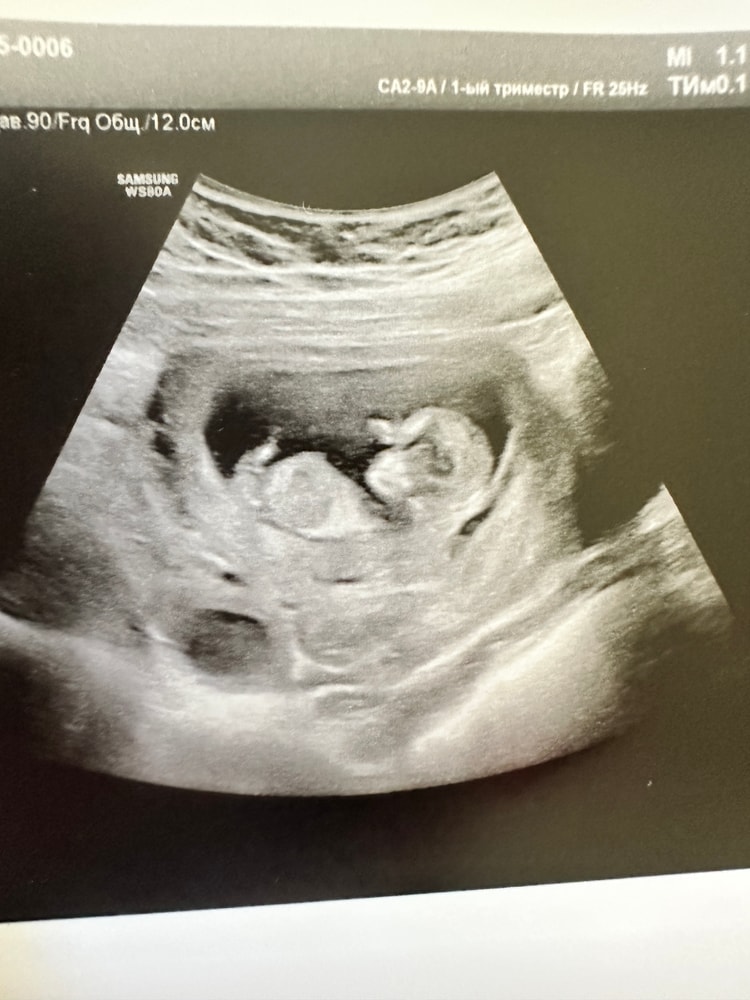

Пол малышаВсем привет! Сегодня была на первом скрининге, срок 12+2, хочу погадать на половом бугорке🤭Видно ли что-то? Вопрос к знатокам в этой области, я профан😀

Fizzy Cherry, на нижнем фото за первой ножкой белая полосочка, конечно фото бы немного другое, но у дочери моей примерно такое же было. А у сыновей сразу под углом достоинство "торчало"))

Сегодня была на УЗИ врач пол смотрела сначала через брюшную стенку: вот половой бугорок, если он смотрит вверх, прям задран, то 85-90% это мальчик, у девочек он более горизонтально сглажен. Потом врач посмотрела ещё трансвагинально и сомнений по поводу пола у нее не осталось